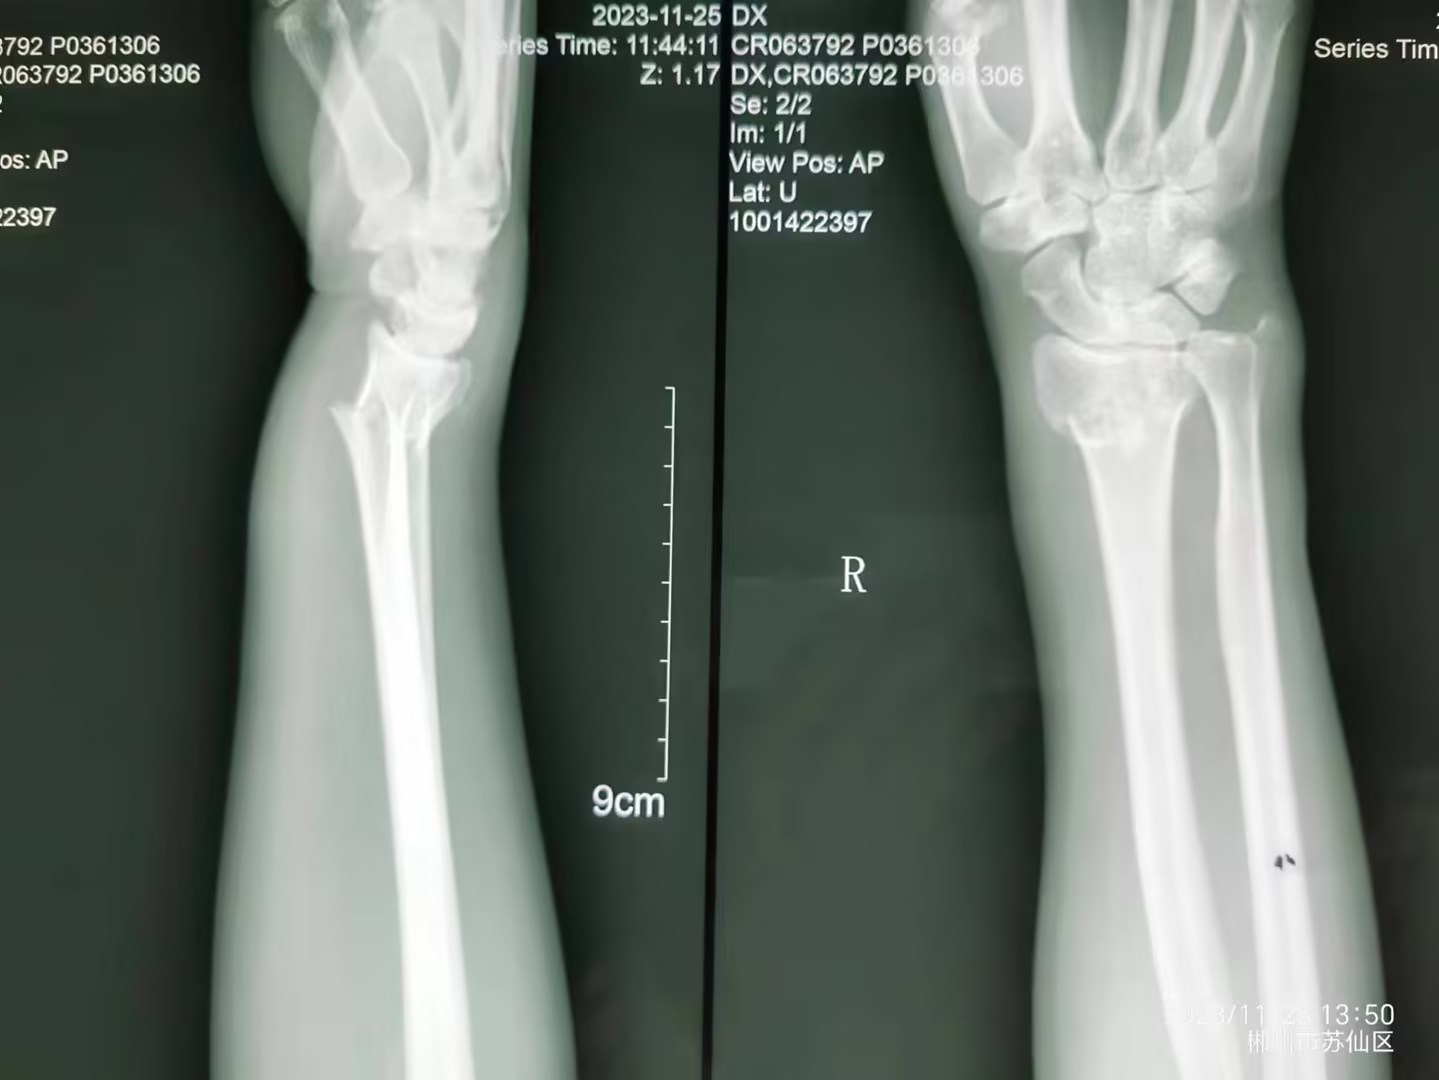

外伤后致右桡骨远端骨折(伸直型)

外伤后致右桡骨远端骨折(伸直型),急诊予手法复位+夹板外固定